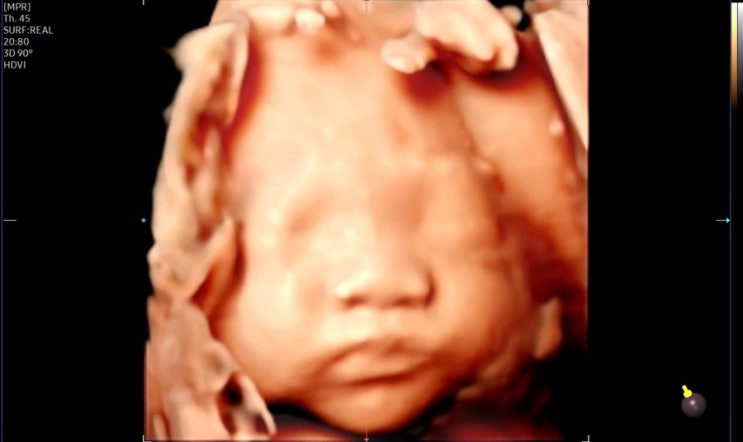

광복이 일기 | 33w 먹방이슈 광복이 복부비만되다

3월은 33주진입 !!! 더 부지런히 움직여야하는데 뭔가 더 먹는 느낌이다 이번주에는 광복이 초음파 보러간...